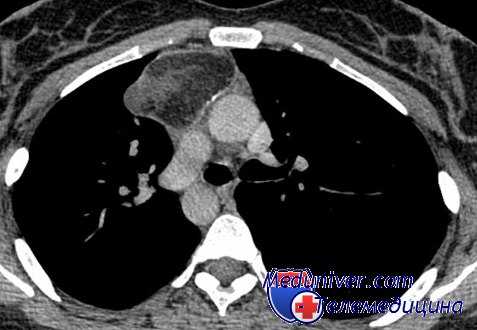

Лимфомы медиастинальной локализации не всегда диагностируются при рентгенологическом обследовании. Компьютерная томография, более детально, чем обзорная рентгенография позволяет рассмотреть конгломерат опухоли, увеличение лимфоузлов средостения, вовлечение паратрахеальных, трахеобронхиальных, прикорневых лимфатических узлов. Диагностическая значимость магнитно-резонансной томографии в верификации лимфом средостения признается не всеми авторами.

КТ ОГК. Объемное образование в средостении (патологически измененный лимфоузел), подтвержденная лимфома.